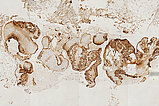

Histopathological section; hematoxylin & eosin (HE) stain, 90x magnification of the punch cylinder. Punch cylinder showing parts of venous malformation with densely packed, irregularly configured large-caliber venous vessel parts. These do not appear tubular as in a normal mature vessel, but as if the vessels are "everted". The lumen looks solid and blood is all around the outside.

Histopathological section; hematoxylin & eosin stain (HE), 160x magnification of the punch cylinder. Here it is clear to see that the irregular, blood-filled spaces of the venous malformation are not solid, but are "voids" partially filled with erythrocytes. The endothelial lining corresponds to the outer border of the visible lesion.

Histopathological section; CD31 stain for specific staining of vascular endothelial cells, which then stain dark brown. 80x magnification of the punch cylinder. This proves that the outer cellular boundary of the visible lesion corresponds to blood vessel endothelia.

Histopathological section; Elastica van Gieson (EvG) staining of collagen and connective tissue. 90x magnification of the punch cylinder. EvG connective tissue staining illustrates the dysplastic wall structure of the malformation with yellow-stained smooth muscle fiber tracts intermixed with red-stained connective tissue areas and interspersed delicate black elastic fibers. This structure is actually typical of venous vessels, but the irregular structure depicted here is atypical and indicates the malformed venous wall structure of the venous malformation.

Histopathological section; the immunohistological staining against smooth muscle actin (SMA) demonstrates the irregular, dysplastic wall structure of the vessels of the venous malformation particularly well. A normal, ordered smooth muscle wall structure is not present. The lesion is asymmetrically interspersed with irregular SMA-positive smooth muscle.

Histopathological section; immunohistological staining using MIB-1 for the Ki67 antigen is a classic stain to show the proliferation activity of a lesion. As a proliferation marker, Ki67 indicates all cells undergoing cell division in the broadest sense (outside the G0 phase in the cell cycle). Here, only very few actively dividing nuclei (here without mitotic spindles) are detectable as positive nuclear staining. Thus, a very low proliferation rate is an indication of a benign lesion.

Purely histopathological diagnosis of a lesion as a venous malformation under the microscope is hardly possible without corresponding clinical information and appropriate clinical referral. Nevertheless, there is good evidence that will characterize a venous malformation based on immunohistology and morphology. The venous malformation is a spongy, blood-filled lesion without any real solid parts, similar to a Swiss cheese with a lot of air (air holes = blood-filled cavities; cheese = dysplastic, venous wall structures). Thus, the actual dysplastic vein walls make up only a fraction of the volume in the overall blood-filled lesion and usually appear irregularly branched like a foxhole rather than tubular.

Immunohistochemical staining with CD31 (blood vessel endothelium) lining the lesion, and the irregular, sometimes patchy, asymmetric surrounding of smooth muscle cells (SMA stain) as well as evidence of atypical collagen and elastic fibers (EvG stain) distributed in the venous vessel wall make the diagnosis highly probable. Venous malformations show little proliferative activity (MIB-1). The histopathologically very similar-looking lymphatic malformation can be well differentiated by D2-40 (podoplanin) staining, which specifically stains only lymphatic vessel endothelia.